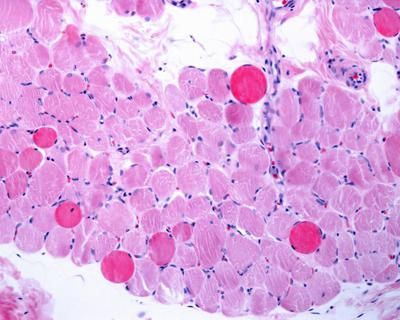

Le malattie tiroidee colpiscono oltre 2 milioni di italiani, con netta prevalenza femminile, ricorda l’Ame. Nel 2024 sono stati diagnosticati oltre 11mila nuovi casi di tumore tiroideo, con prognosi generalmente favorevole, ma necessità di follow-up costante. “La gestione del tumore tiroideo – spiega Rinaldo Guglielmi, coordinatore della Commissione tiroide Ame – è oggi guidata dalle nuove linee guida dell’Ata – American Thyroid Association, che privilegiano strategie conservative e attenzione alla qualità di vita dei pazienti”. Aggiunge Enrico Papini, coordinatore del Comitato scientifico Ame: “Le linee Guida 2025 della European Thyroid Association chiariscono inoltre la gestione dell’ipotiroidismo primario, un problema apparentemente semplice ma di grande impatto sulla qualità della vita”. Per quanto riguarda sovrappeso e obesità, l’Italia è al quarto posto in Europa per prevalenza nell’età infantile. La recente legge Pella riconosce l’obesità come malattia cronica e la inserisce nei Livelli essenziali di assistenza. “In Italia l’obesità resta un’emergenza silenziosa che coinvolge oltre 6 milioni di persone – sottolinea Marco Chianelli, coordinatore della Commissione obesità Ame – Servono misure efficaci di prevenzione e trattamento”. Le nuove terapie, come semaglutide e tirzepatide – concludono gli esperti – consentono una riduzione media del peso del 20% e migliorano le complicanze metaboliche.